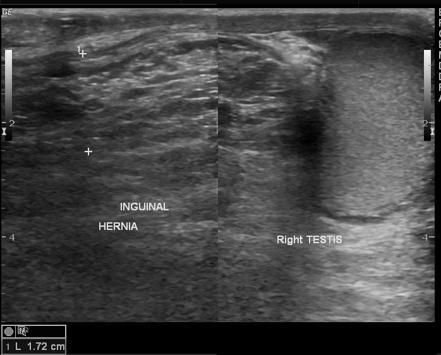

swollen scrotum

persistent or intermittent palpable mass

abdominal pain

blood in stool

Scrotal Hernia